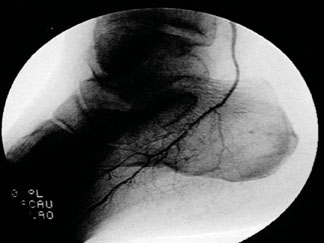

Even lower profile atherectomy technologies are available that allow endovascular interventions below the ankle and to the pedal, or what I have termed “infrapedal”vessels.Vascular interventionalists can now deliver coronary wire-based 0.014-mm wires even into digital vessels.

The 0.9 excimer laser probe, which has been available for several years, allows pedal atherectomy and revascularization. The new MiniHawk plaque excisional device (ev3) is now less than 2 mm in diameter and can infiltrate into pedal vessels. The recently available Diamondback 360 orbital atherectomy device (Cardiovascular Systems) also has a very low profile.Vascular interventionalists can utilize this device in infrapopliteal and pedal vessels with this design being particularly helpful in those highly calcified vessels that we see in diabetic and dialysis patients.